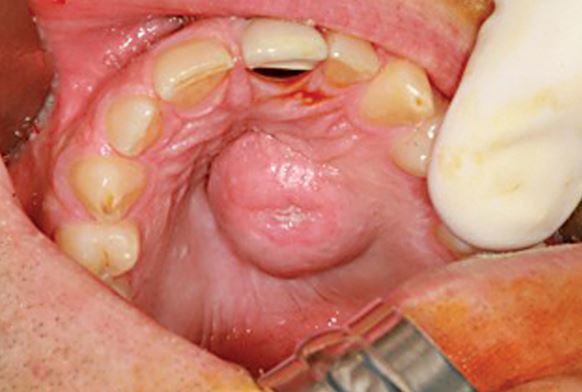

White colored bumps on the tongue and areas in your mouth especially on your palate can easily be tumors that could become cancerous. If you notice even a small bump on your palate, rush to a doctor immediately.

Image Source: www.treatcurefast.com